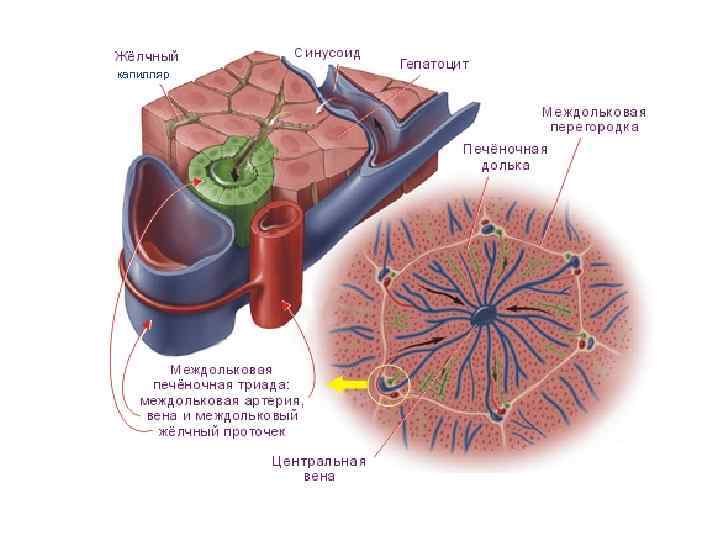

ПЕЧЕНЬ ЧЕЛОВЕКА

капилляр

капилляр

Холангиола

CV- центральная вена BD- желчные протоки * - синусоидные капилляры

1 - зона оптимального кровоснабжения, 2 - зона умеренного кровоснабжения, 3 - зона наихудшего кровоснабжения (наиболее уязвима при интоксикациях)

Препарат № 138 «Печень свиньи»

Триада печени

Препарат № 139 «Печень человека»

Препарат № 139 «Печень человека»

Препарат № 139 «Печень человека»

Триада печени

Печень человека. Окраска кармином (выявление сосудов)